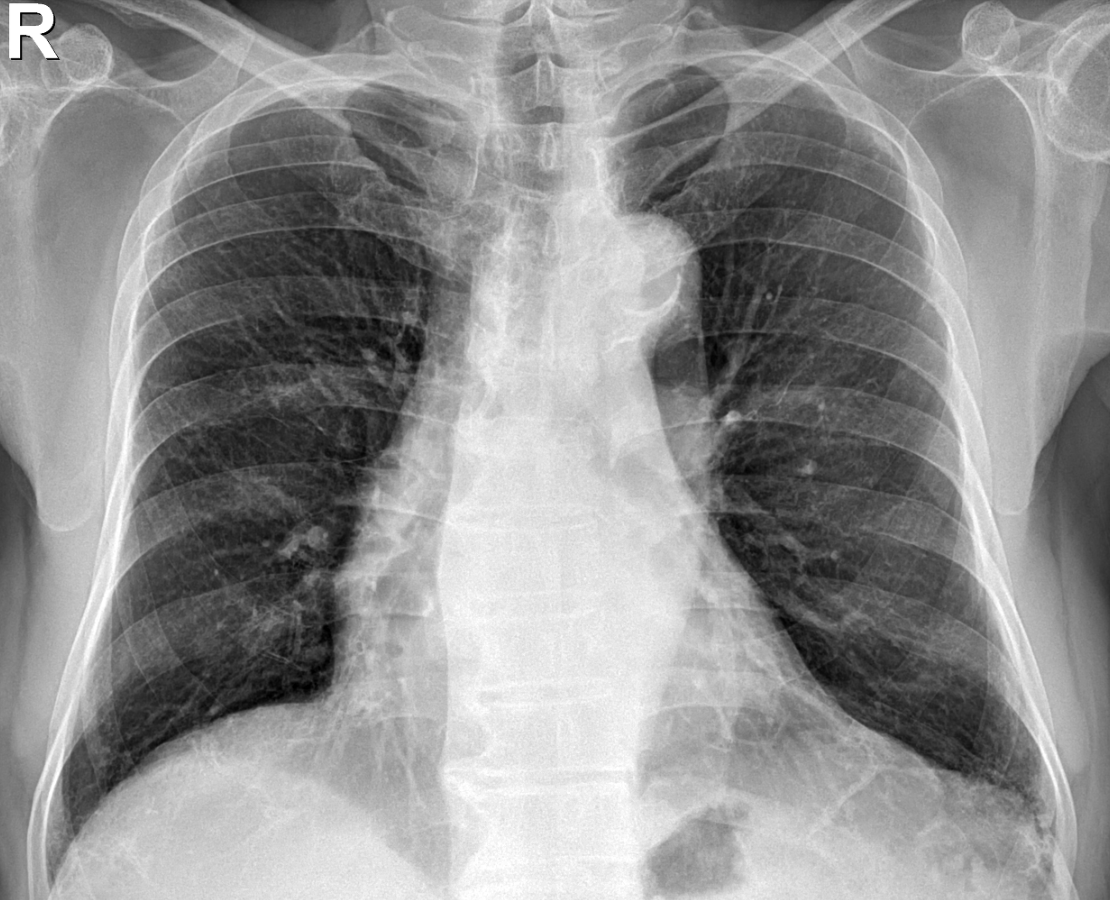

흉막 비후는 흉막이 두꺼워진 것을 말합니다. 보통 흉부 엑스레이나 CT 촬영으로 많이 확인하는 상탭입니다. 흉막은 폐를 둘러싸고 있는 얇은 막으로, 폐가 부드럽게 움직일 수 있게 도와주는 역할을 합니다.

그런데 여러 이유로 흉막이 두꺼워지는 경우가 있습니다. 이를 흉막 비후라고 부르며, 이는 폐나 흉막에 무언가 자극이 있거나 염증이 생기면서 발생할 수 있습니다.

4) 흉막 삼출

흉막 삼출은 흉막 사이에 액체가 많이 쌓이는 상태로, 그로 인해 흉막 비후가 발생할 수 있습니다. 흉막 삼출이 있을 때 흉막이 두꺼워지며, 간경변이나 심부전도 흉막 비후 원인이 될 수 있습니다.

심장 가까이에 있는 심횡격막 부위 흉막도 비후가 잘 생기는 부위 중 하나입니다. 이 부위의 비후는 다음과 같은 이유로 발생할 수 있습니다.

● 심부전: 심장 기능이 약해지면서 심장 주변에 체액이 고일 수 있고, 이로 인해 흉막이 두꺼워질 수 있습니다.

● 심장 관련 염증: 심장 근처의 염증이 흉막에 영향을 주어 비후를 일으킬 수 있습니다.